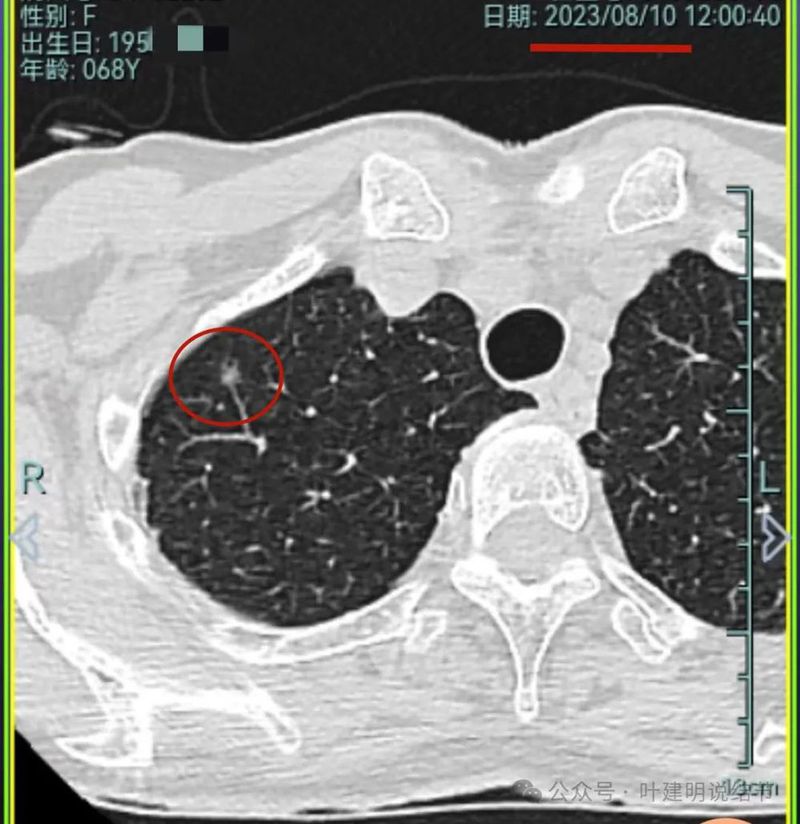

再看2023年8月的影像:

病灶1没什么进展。

病灶2与前相仿。

病灶3仍混合密度,说不上显著进展。

病灶4 仍是钙化的,大小也没有进展。

病灶5较前密度又有增高,贴着叶间裂,整体轮廓显得较之前清楚些,更符合恶性表现了,而且应该是浸润性腺癌。

病灶6与前相仿。